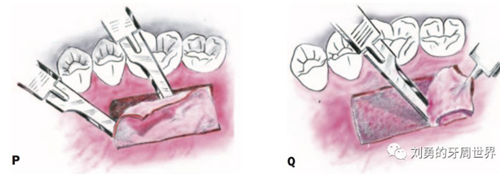

1、最常從上頜硬腭取瓣,在取瓣區(qū)域(一般要避開前牙區(qū)域的腭皺襞,一般在3的遠(yuǎn)中)局麻下,紙片放置在取瓣區(qū)域近齦緣的區(qū)域(距離齦緣2-3mm),15號(hào)刀片劃出取瓣輪廓(O)

2、然后用15號(hào)刀片半厚瓣的方式取瓣,如下圖:

3、將移植瓣放濕鹽水紗布上保存。然后縫合供區(qū)止血(R)

4、將移植瓣去除脂肪腺體,放在鹽水紗布上修整確保表面光滑、厚度均勻(S、T)